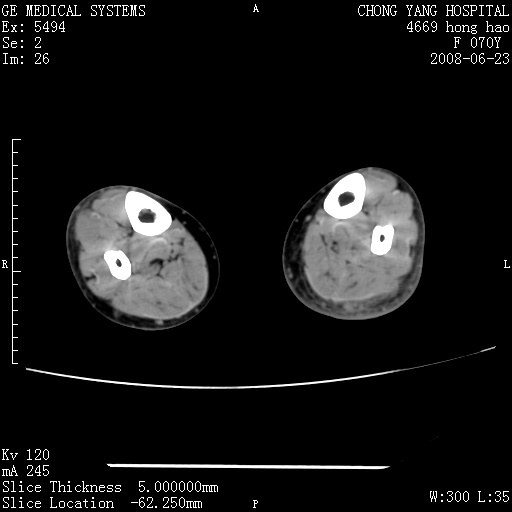

以下是引用zsl6918在2008-6-24 23:07:00的发言:[br]皮下脂肪影模糊,密度增高,但未见具体肿物影,考虑蜂窝组织炎可能性大。

以下是引用zjzjr在2008-6-24 21:44:00的发言:[br]皮下软组织肿厚,脂肪间隙混浊,考虑感染.

以下是引用peijunlong在2008-6-24 20:56:00的发言:[br]左小腿后方软组织皮下脂肪间隙见条片状密度增高影,范围较大,相邻皮下见条索影。[br]考虑:无菌性炎症可能性大[br]鉴别:主要与蔓状血管瘤鉴别,蔓状血管瘤也可表现为软组织内葡伏生长的扁平状的软组织密度影,但它的范围更大,且主要在软组织内,肌间隙中,皮下脂肪间隙内罕见。